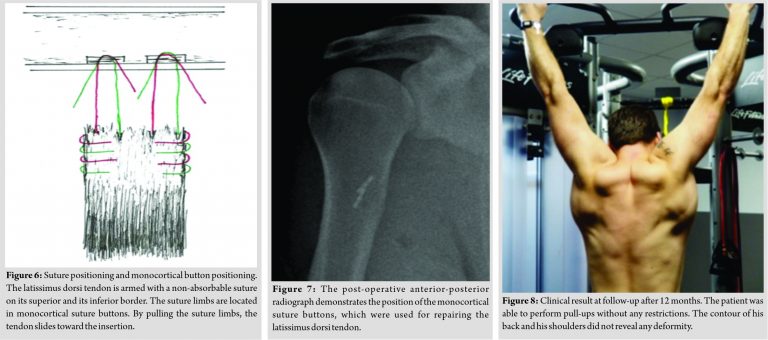

The patient was positioned in a lateral decubitus position on his left side. A mechanical arm-holder (Trimano Arthrex Inc., Naples, Florida) secured the right arm in a position of 90°abduction, neutral rotation (Fig. 2). A 10cmskin incision was made along the posterior margin of the deltoid muscle in the posterior axillary fold. After identification of the teres major muscle, the adhesions of the LDM were released and a Langenbeck retractor was inserted to lift the teres major muscle cranially to expose the insertion of the LDT (Fig. 3).Subsequently, the retracted stump of the LDT was identified and mobilized manually. A forceps was used to assess the tension of the LDT while moving it toward its insertion (Fig. 4, Video 1). Subsequently, the LDT was armed with two non-absorbable sutures (Fiber-Wire No. 2, Arthrex Inc., Naples, Florida), thus creating a proximal and a distal pair of suture limbs (Fig. 5 and 6). The crest of the lesser tuberosity was identified beneath the insertion of the teres major tendon and abraded to a bleeding surface with a rasp. The free ends of each paired suture were passed through the 12-mm tension slide button (Distal BicepsButton, Arthrex Inc., Naples, Florida) in an alternating fashion. After drilling two 3.2-mmmonocortical holes with a distance of 3 cm into the insertion of the LDT, the proximal and the distal button were inserted with the provided inserter. Pulling on the suture limbs flipped both monocortical buttons, thus preparing the tension-slide reinsertion of the LDT (Fig. 6). Afterward, the suture limbs were pulled tight and secured with seven half hitches for each button. After the procedure, the LDT showed an optimal attachment to its insertion.

The post-operative radiograph demonstrated the position of the monocortical suture buttons in the humerus (Fig. 7).

Twelve months after the surgical procedure, the patient-rated his subjective shoulder value of the right shoulder with 90%. The patient did not report any rest pain or stress pain. The range of motion of the right shoulder was unrestricted. The patient was already able to perform most of his weight-lifting exercises and CrossFit exercises. (Fig. 8) demonstrates the athlete while doing a pull-up exercise in the gym.